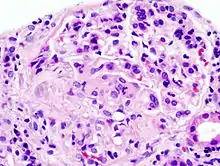

![]() Imagen histopatológica de una muestra de glomerulonefritis con semilunas obtenida de un paciente con glomerulonefritis rápidamente progresiva positiva para anticuerpos anti-MPO-ANCA. Tinción con hematoxilina y eosina. | ||

Pese a la gran variedad de enfermedades que causan glomerulonefritis rápidamente progresiva, todos los tipos se caracterizan por daño glomerular y formación de semilunas. El daño más grave y la ruptura de la membrana basal glomerular conducen a la pérdida de proteínas plasmáticas. De estas proteínas, se piensa que la fibrina es la que más contribuye a la formación de semilunas. Las células epiteliales que delimitan la cápsula de Bowman responden al estímulo proliferante de la fibrina. También puede haber infiltración de leucocitos como los monocitos y los macrófagos, los que también pueden proliferar bajo la influencia de la fibrina. Estas células proliferantes rodean al glomérulo y lo comprimen por lo que aparece la cicatriz con forma de semiluna que es visible con el microscopio en el material obtenido de una biopsia renal.[2]

Anatomía patológica

En la biopsia de estos pacientes se halla una importante proliferación de las células epiteliales de la cápsula de Bowman, con formación de semilunas en los glomérulos.[4] La biopsia renal confirma la presencia de una glomerulonefritis con semilunas epiteliales. Entre las características histopatológicas figura la infiltración del espacio urinario por células mononucleares asociada con la proliferación del epitelio parietal de la cápsula de Bowman o la proliferación extracapilar con formación de semilunas que pueden afectar del treinta al cien por ciento de los glomérulos. En estos se ve un engrosamiento de la cápsula de Bowman con formación de semilunas. También puede haber fibrosis parcial y sinequia del penacho glomerular a la cápsula.[4] Las semilunas, que pueden ser segmentarias o circunferenciales, ocupan todo el espacio de Bowman y ahogan el ovillo capilar, según el estado evolutivo pueden clasificarse en celulares, fibrocelulares o fibrosas y representan fases progresivas del mismo proceso.[4] En la glomerulonefritis rápidamente progresiva de tipo I hay positividad lineal sobre todo para IgG pero después también para C3. Dos tercios de las glomerulonefritis semilunares de este tipo corresponden al síndrome de Goodpasture y el otro tercio carece de manifestaciones pulmonares (síndrome de Goodpasture sin compromiso pulmonar). La lesión glomerular es similar en ambos grupos y se produce por un mecanismo inmunitario antimembrana basal glomerular. Como ya se dijo, el factor desencadenante es un defecto de un componente proteico de la cadena α3 del colágeno de tipo IV.[5] En la enfermedad de tipo II hay positividad granular o nodular o de ambas formas, difusa y global, debido a depósitos de complejos inmunes que con el microscopio electrónico se ven como depósitos densos. Este tipo por lo general corresponde a variedades de la glomerulonefritis aguda difusa, de la glomerulonefritis mesangiocapilar y, menos a menudo, de la enfermedad de Berger.[5]

Por último, en la glomerulonefritis semilunar de tipo III el examen con inmunofluorescencia es negativo y los hallazgos detectados con el microscopio electrónico son similares a los de la enfermedad de tipo I (sin depósitos densos). Si bien se ignora la patogenia de esta lesión glomerular, se piensa que en una buena cantidad de casos la causa de la ruptura de capilares glomerulares y de la proliferación celular glomérulo-capsular sería una vasculitis o una angiopatía. Este cuadro se observa con mayor frecuencia en adultos mayores.[5]